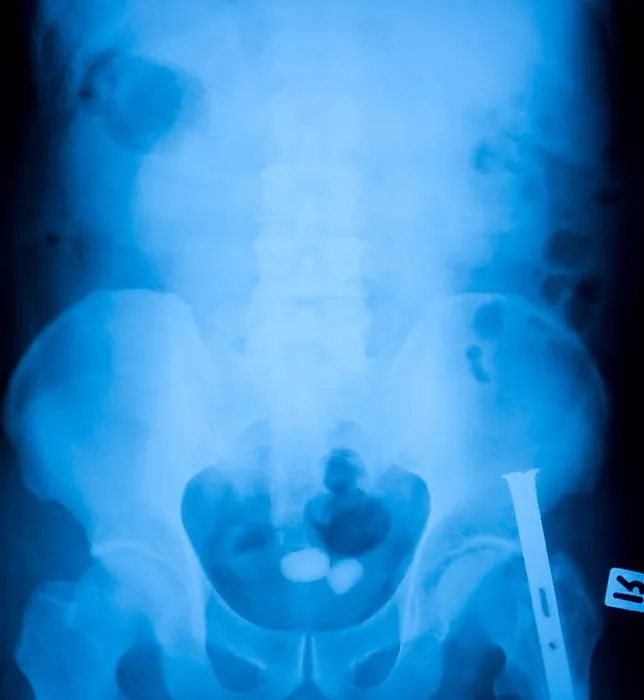

Отсутствие тени на обзорной рентгенограмме не исключает наличие камня мочевого пузыря. Примерно в 50 % случаев камни не определяются на обзорных рентгенограммах. Рентгенонегативный камень можно выявить при цистографии. Лучшим и наиболее точным методом диагностики камней мочевого пузыря является цистоскопия. Ни один камень не будет пропущен при непосредственном осмотре мочевого пузыря.